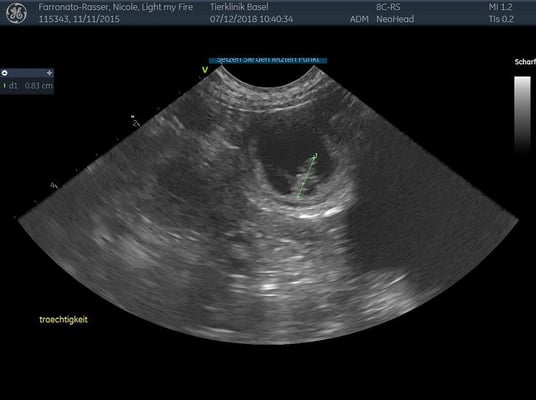

7. Dezember 2018. Der heutige Ultraschall am 24. Trächtigkeitstag hat gezeigt, dass Light trächtig ist! Wir freuen uns riesig auf Mitte Januar und hoffen auf eine Kiste gesunder kleiner Labradore!